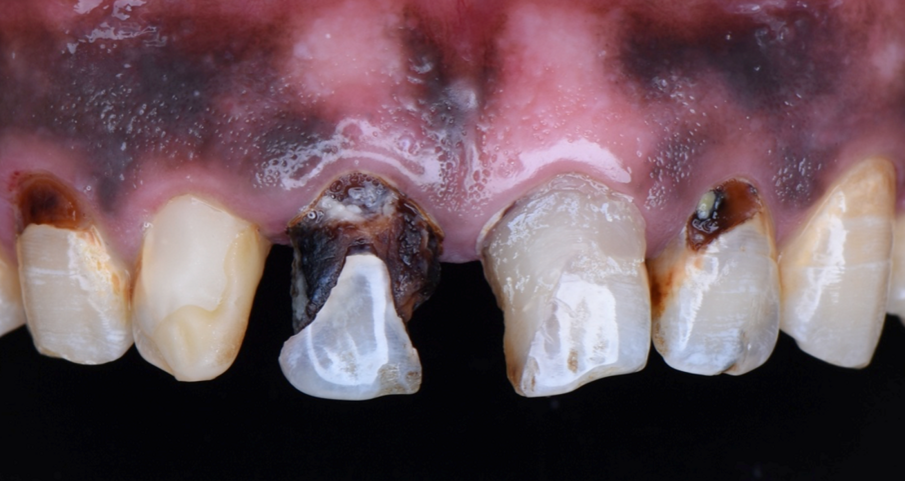

A 44 year-old male patient came to the clinic to solve his aesthetic problem related to incisors, canines 13, 12, 11, 21, 22.

Before